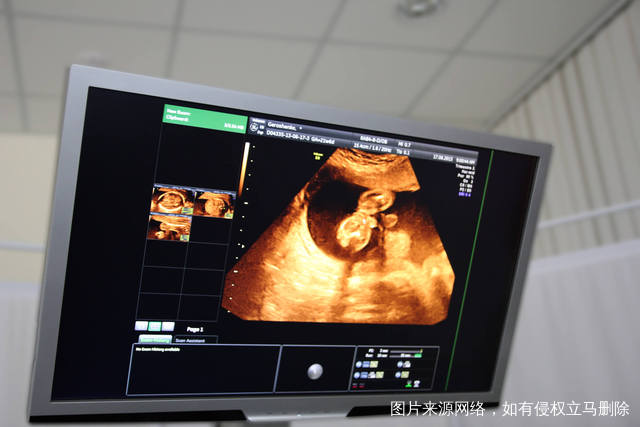

3、郑州哪个医院有三代技术

现在试管技术已经更加进步了,如果还在选择一代或是二代技术,确实会有着一些无法避免的问题,当然也不是朋友们的理想选择。可以尝试三代手术的话,相信大家也会更加放心,上面提到的医院,都掌握着三代技术,朋友们能够进行更多询问。

了解到这里之后,关于郑州哪个医院做试管婴儿最好?以及三代技术怎么样,认真看过介绍内容的朋友,都可以知道答案到底是什么了。三代之所以更受欢迎,就是由于能够保证试管宝宝更健康,有遗传病基因也能被检测出来,优势当然非常多。